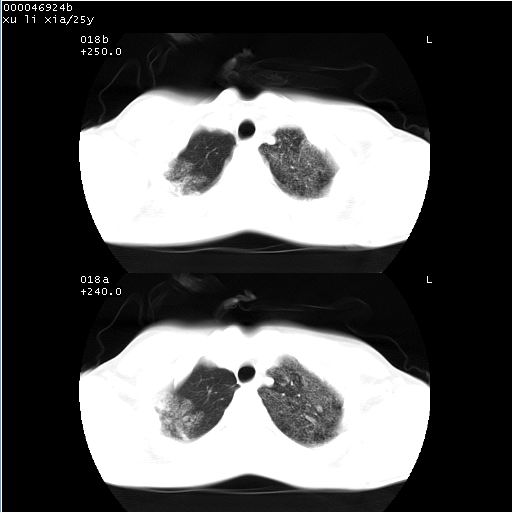

胸部ct轴位平扫(层厚10mm,螺距1.5,重建间隔10mm),图像如下:

病灶呈地图样分布于肺外围,与正常组织分界清晰+弥漫性磨玻璃影中见小叶间隔增厚呈碎石路样表现+年轻女性,无明显临床症状=肺泡蛋白沉积症?

双肺上叶可见节段性渗出性病变,可见树芽征像,左肺下叶背段可见结节影。

病灶呈离心性分布,以两上肺多见,远离肺血管纹理,有部分肺间质条索影,病人症状轻微,考虑结节病。

平行于间质走行微结节影;拌钙化灶;分布通气好的肺野